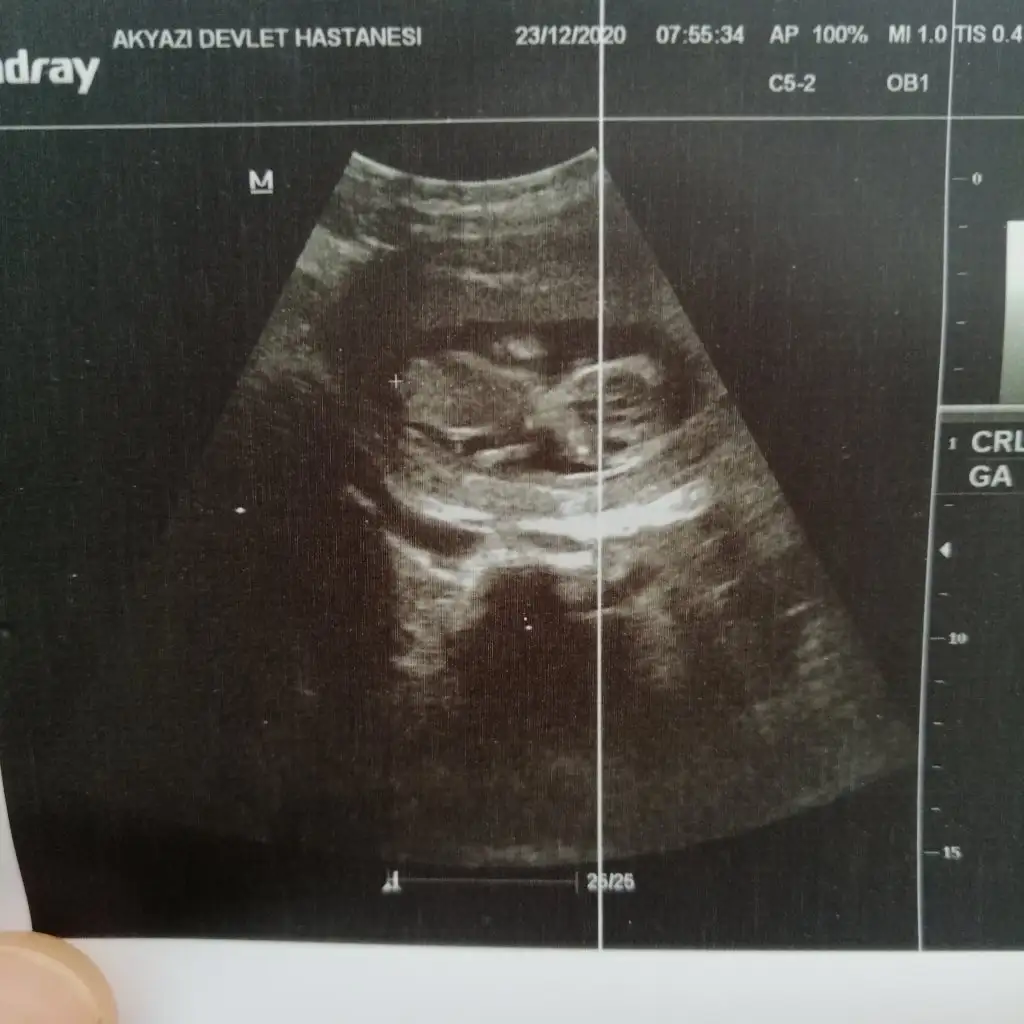

• IMG_20201223_095839.webp

IMG_20201223_095839.webp

41,1 KB · Görüntüleme: 56